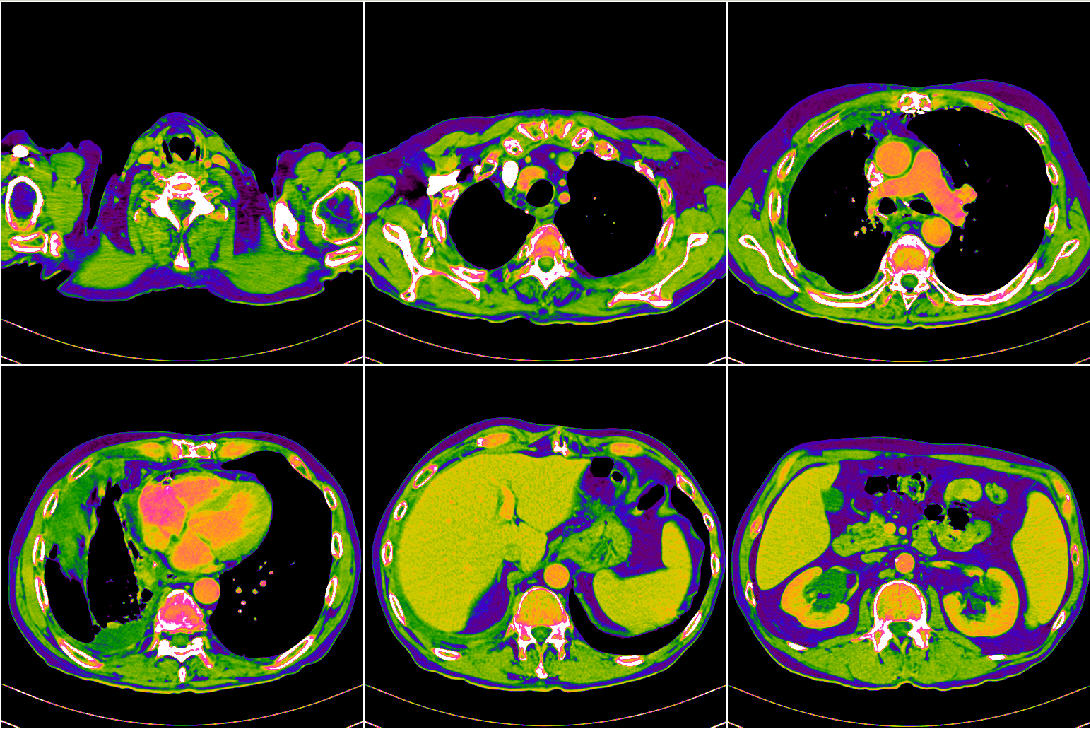

The Cancer Genome Atlas Lung Adenocarcinoma (TCGA-LUAD) 是一个肺癌CT影像数据,源自另一个更大的癌症数据项目 The Cancer Genome Atlas (TCGA),旨在对各种类型的癌症诊治过程进行全程数字化的跟踪,以数字档案的形式记录检查结果、处方和疗效。

| 数据介绍: | The Cancer Genome Atlas Lung Adenocarcinoma (TCGA-LUAD) 是一个肺癌CT影像数据,源自另一个更大的癌症数据项目 The Cancer Genome Atlas (TCGA),旨在对各种类型的癌症诊治过程进行全程数字化的跟踪,以数字档案的形式记录检查结果、处方和疗效。 |